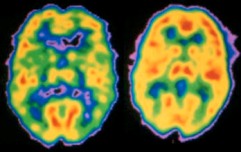

| Pet scan de cerebro de paciente con esquizofrenia (Izq.) y normal (Der.) Univ. Purdue. |